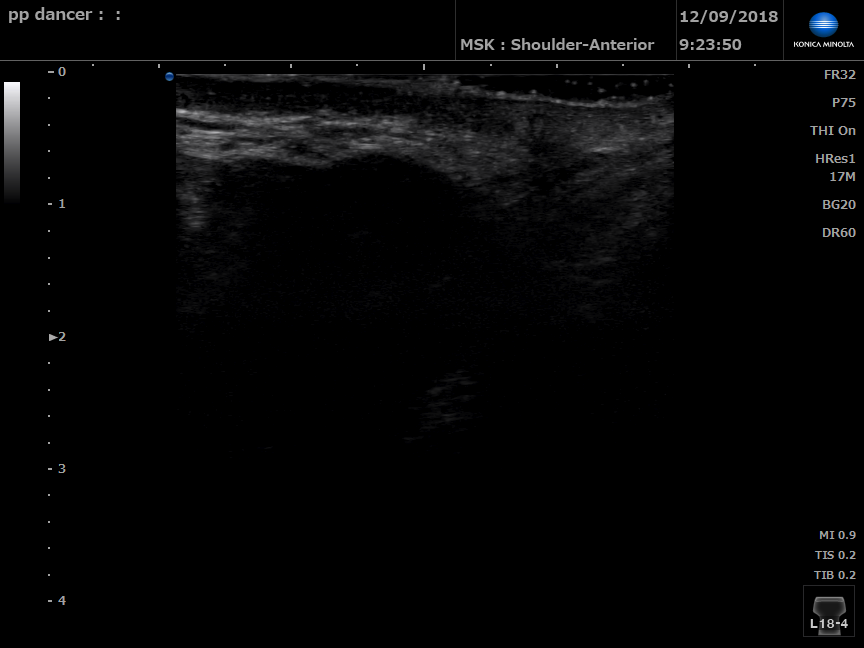

Dancer without pelvic floor dysfunction

B Mode ultrasound of right perineal body